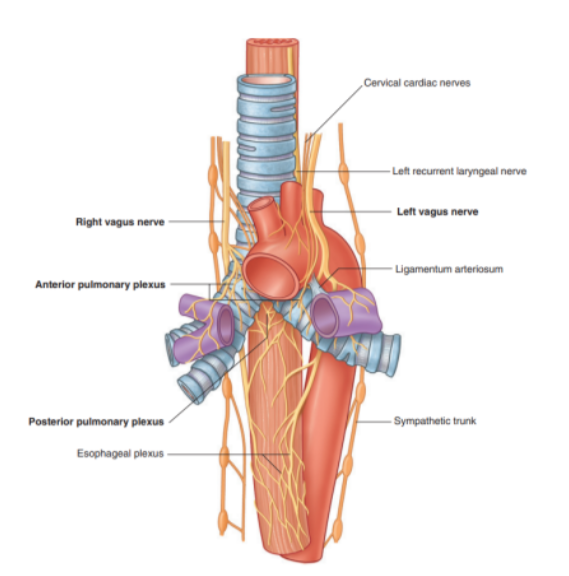

Innervation of the lungs

Nerves of lungs & visceral pleura are derived from the pulmonary plexuses anterior & (mainly) posterior to the roots of the lungs

These nerve networks contain parasympathetic, sympathetic, & visceral afferent fibers

These interconnected plexuses lie anteriorly & posteriorly to the tracheal bifurcation & main bronchi

The anterior plexus is much smaller than the posterior plexus

Branches of these plexuses, which ultimately originate from the sympathetic & vagus trunks, are distributed along branches of the airway & vessels

posterior from vagus, anterior from

The visceral efferents from the vagus system allow the constriction of the bronchiole, those from the sympathetic system dilate the bronchioles